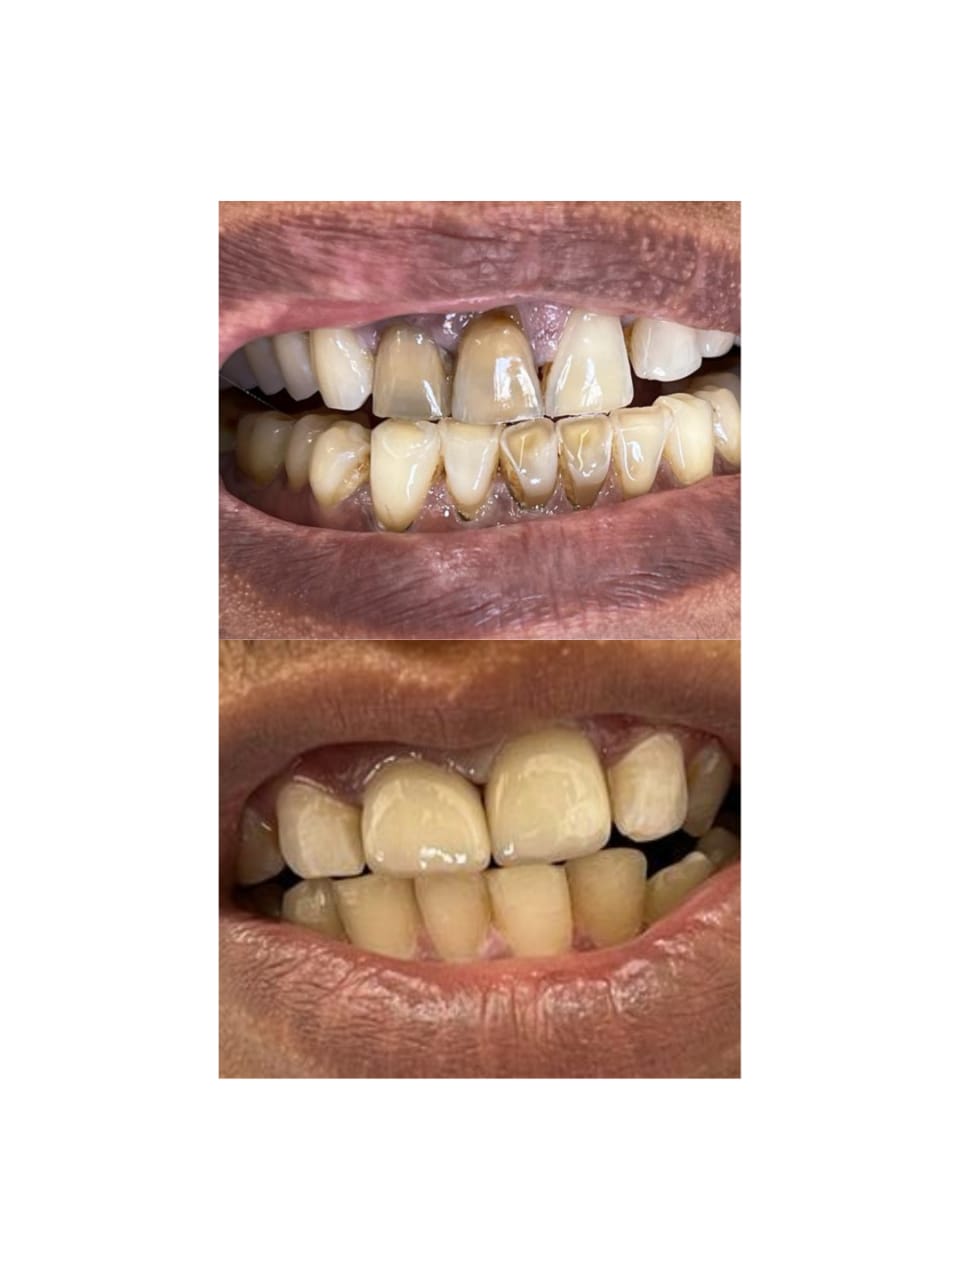

Tooth restorations are the various ways your dentist can replace missing teeth or repair missing parts of the tooth structure. Tooth structure can be missing due to decay, deterioration of a previously placed restoration, or fracture of a tooth.

Both crowns and most bridges are fixed prosthetic devices. Unlike removable devices such as dentures, which you can take out and clean daily, crowns and bridges are cemented onto existing teeth or implants, and can only be removed by a dentist.